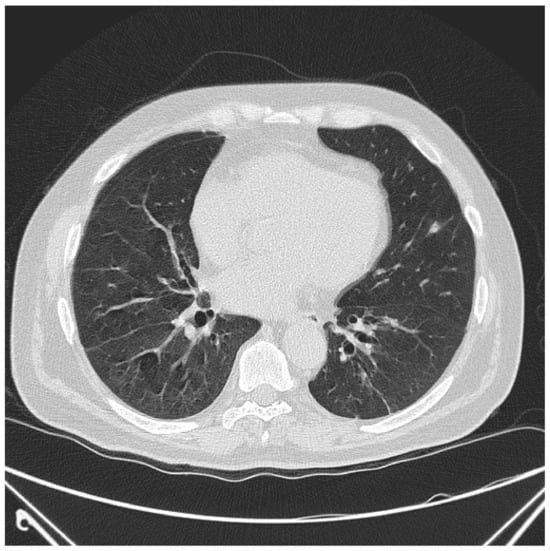

6.2. Histopathologic and Radiographic Findings in Myositis-Associated ILD